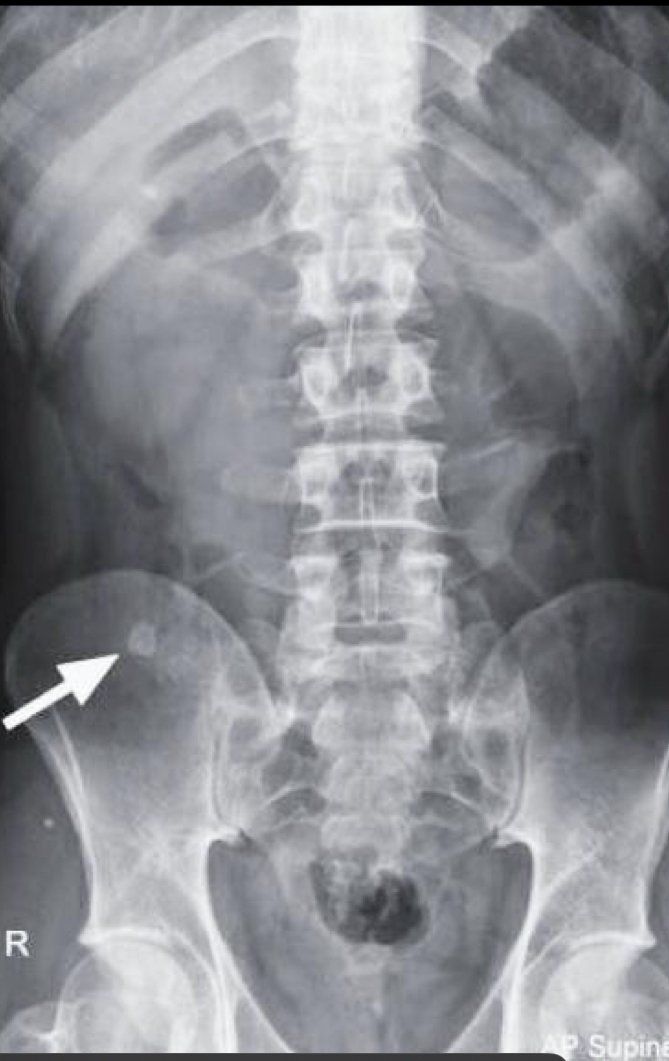

Signos de rx apendicitis q se ven son muchos

• apendicolito -5%

• Borramiento psoas

• Niveles hidroaereos

• Asa centinela

• Hiperdensidad articulación sacroiliaca drch

• Borramiento grasa preperitoneal

• Radioopacidad difusa en FID

• Curvatura antialgica

6

Que es eso

A

hiperdensidad articulación sacroiliaca drch

8

apendicolito